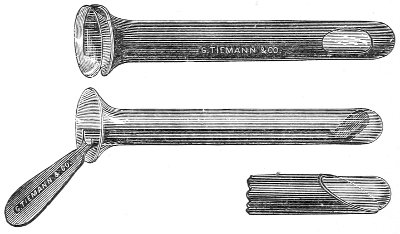

Examination of the Rectum.—If the woman is placed in the knee-chest position, a most satisfactory inspection of the whole of the rectum may be made. The woman should be placed in this position with the buttocks before a good light, and the posterior margin of the anus should be retracted by the small blade of a Sims speculum; the rectum will immediately become distended with air and the rectal walls will be well exposed. Or the rectal specula (Figs. 13, 14) may be used. In employing the longer of these instruments it is best to use light reflected from a head-mirror or thrown directly from an electric head-light into the speculum.

|

|

Fig. 13.—Rectal speculum, large size. |

Fig. 14.—Rectal speculum, small size. |

The instrument should always be introduced for the 34 first two inches with the obturator in place. The obturator should then be withdrawn and the speculum pushed farther in, the operator watching and guiding its course around the rectal valves or folds of mucous membrane, so as to prevent injury to the walls of the rectum. Anesthesia is not necessary for this procedure.